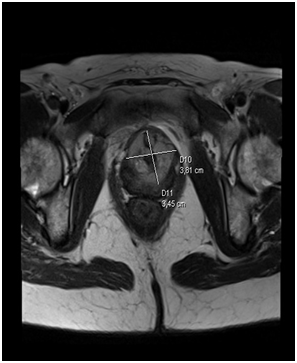

A 54-year old white woman, without significant past medical history other than menopause since 2years ago presented with post coital hematuria and also she had urinary tract infections (UTIs), documented by urine cultures (Proteus Mirabillis). No other associated symptoms. She received antibiotic therapy with quinolones. The urine cytology was negative. The assessment by the Gynecology service was normal. The renal ultrasound (US) Each kidney was normal, preserved cortico medullary differentiation and without dilated collecting systems. There was irregularity zone in the mucosa close to bladder neck, measuring 1x0.5cm. Cystoscopy revealed an edematous and erythematosus lesion of 1x1.5cm in the posterior wall of the bladder neck that extended into the urethra. In pelvic magnetic resonance imaging (MRI) a pelvic mass was evident measuring 35x38x47mm, widening the bladder neck at this level, nonspecific inguinal adenopathies and a left iliac node with malignancy aspect.

Figure 3 Initial pelvic MRI

Radical cystourethrectomy was performed with bilateral pelvic lymph node (extense iliac region) dissection (Figure 4) and anterior vaginal wall excision (vaginoplasty) followed by ileal urinary diversion (Bricker type). Ureteral end edges were sent to frozen biopsy and the results were negative. The specimen’s pathology was “adenocarcinoma with clear cell areas and focus of papillary, located in the trigone region, affecting the peri vesical tissues without infiltrating the muscular layer of the vagina (pT4a). Bilateral pelvic lymph nodes were free of tumor (12 nodes in the left side and 14 in the right side), like the rest of organs. Neoplasia stage: pT4a pN0 pM0”.